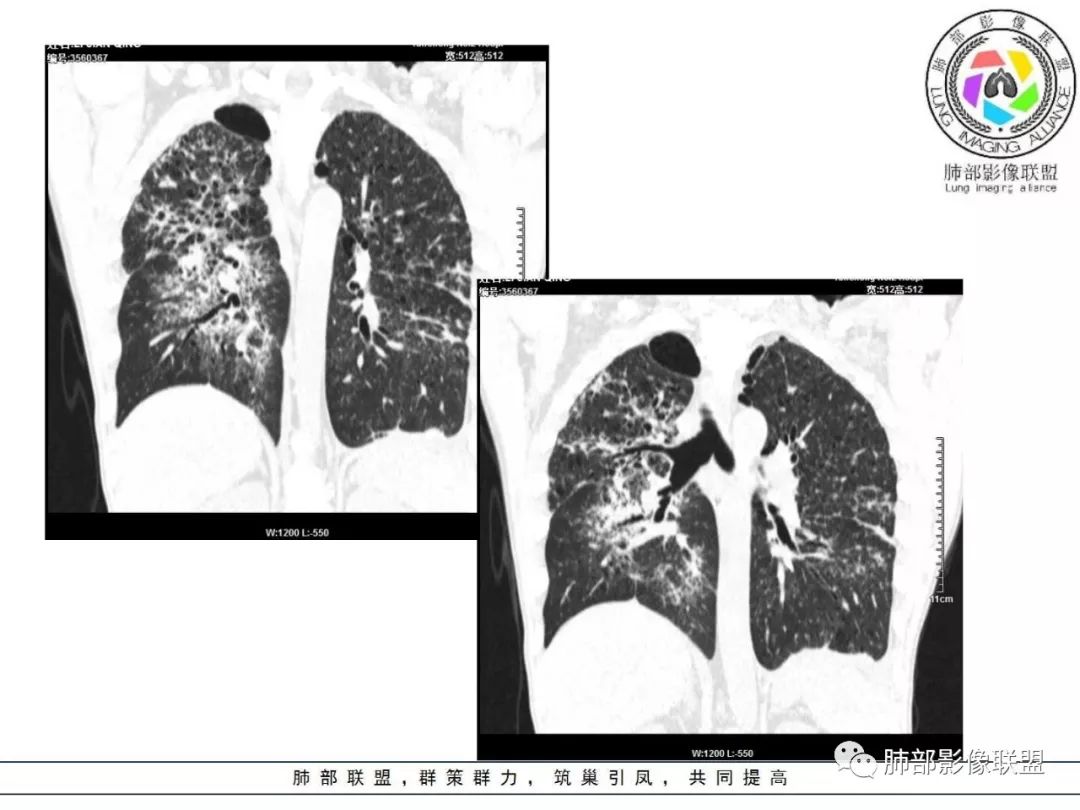

胸部CT:两肺弥漫病灶,磨玻璃影,少许实变,部分累及胸膜,磨玻璃区可见囊?少许胸腔积液,两肺可见结节,支气管血管束增粗,小叶间隔增厚,支气管走形有扭曲扩张,可见纤维化。气肿、大泡。考虑:感染性病变,PCP?查下HIV,CD4,G等。鉴别结核、结缔组织病肺浸润。

55多男性,发热为主诉,体温38℃-39℃多,午后及夜间发热为主,峰值40℃,伴黄痰,CRP高,血糖正常,胸部CT:两肺弥漫病灶,磨玻璃影,少许实变,部分累及胸膜,两肺可见结节,似可见树芽,支气管血管束增粗,小叶间隔增厚,见肺气肿、大泡。考虑感染性病娈,肺结核可能性大。

胸部CT:两肺弥漫病灶,中央间质分布为主,部分位于胸膜及叶间裂旁,磨玻璃影,斑片影,部分实性结节,肺气囊,支气管血管束增粗,小叶间隔增厚,叶间裂不均匀增厚,支气管走形有扭曲扩张,可见纤维化、气肿、大泡。考虑:LIP加MALT。鉴别PLCH、PCP、结核、结缔组织病肺浸润。

中老年男性,双肺弥漫性病变,呈网状、斑片及大片状,实变影及磨玻璃影相间,部分病灶区支气管扩张,并见多发小囊状或蜂窝状透亮影,中央间质增厚,气管前单发小淋巴结。考虑淋巴细胞增生性病变?粘膜相关性淋巴瘤(MALT)或淋巴细胞间质性肺炎(LIP)?鉴别机化性肺炎(OP)及结核(TB)。

两肺弥漫性病变,沿支气管血管束分布,部分细支气管轻度扩张,两上中肺为主,部分累及胸膜下,部分磨玻璃影,部分纤维化,肺气肿肺大疱背景,胸膜增厚,少量积液,病程一月余,crp高反复发热,两肺门区增大钙化淋巴结,间质性疾病,考虑淋巴增殖性病变为主,结核可能性大,待鉴别NTM,结节病,LIP,PCP纤维化

中老年男性,发热1月余,双肺弥漫性病变,多发网格、结节、斑片状实变影及磨玻璃影,胸膜下及中轴间质都受累,支气管血管束增粗、变形,支气管扩张,叶间裂及小叶间隔增厚,整体间质性改变明显,考虑结核?OP、LIP?进一步除外PCP、肿瘤、结节病等。

病灶呈片状磨玻璃密度影,呈典型的烟花征。磨玻璃影密度偏高,有网结节样改变,与正常肺实质分界清楚,且常见相对高密度的勾画。

常会伴有其他继发性肺结核病灶,如斑片影、结节影,树芽征,新旧不等改变。

2. 肺气肿背景(小叶中心性肺气肿);双肺多发病灶整体沿血管支气管束及胸膜下分布,以上叶及下叶背段分布为主,有实变及GGO,边界清楚,有树芽,小叶间隔及中央间质增厚,叶间裂见到多发结节,部分支气管不规则牵拉扩张,提示病灶纤维化明显,结合临床病史,考虑病灶为间质性感染,肺门及纵隔内有钙化淋巴结,小叶间隔结节,考虑淋巴道增值性疾病可能,综合常规要怀疑间质性肺结核。